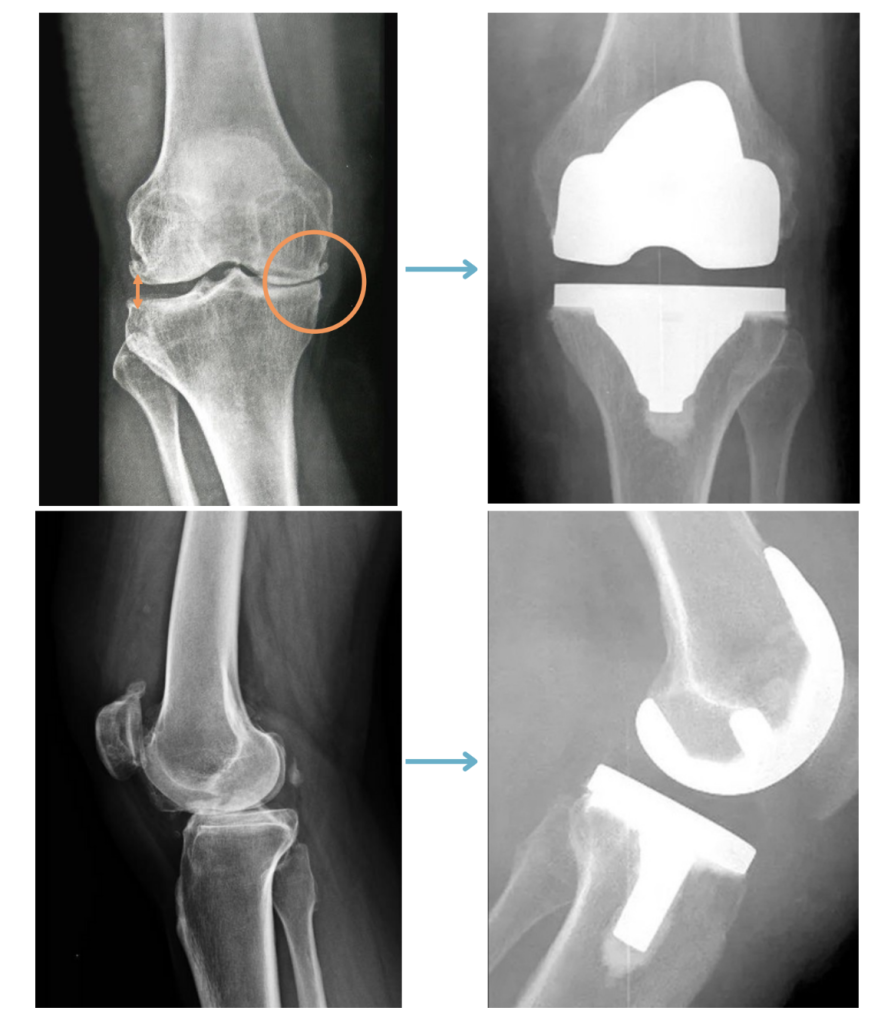

Se trata de um procedimento de substituição articular, indicado em casos graves e avançados de artrose, onde iremos substituir as estruturas do joelho que estão desgastadas e sem cartilagem, por componentes metálicos e de polietileno (plástico super resistente), especialmente projetados para restaurar a função do joelho.

É muito comum pensarmos que, durante a cirurgia de prótese total, toda a articulação do joelho será trocada e substituida por um joelho novo, porém, na verdade, o que ocorre é que substituimos apenas as superfícies que estão desgastadas e tentamos preservar o máximo possível do joelho original.

Na figura acima, podemos entender um pouco mais sobre a prótese total de joelho e seus componentes. Os implantes metálicos femoral e tibial, são fixados ao osso, através de um cimento ortopédico especial.